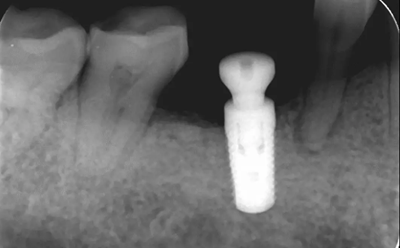

16、修復(fù)前根尖片

二期術(shù)后1月根尖顯示種植體周?chē)琴|(zhì)穩(wěn)定,無(wú)進(jìn)一步吸收。

(2018年5月25日)